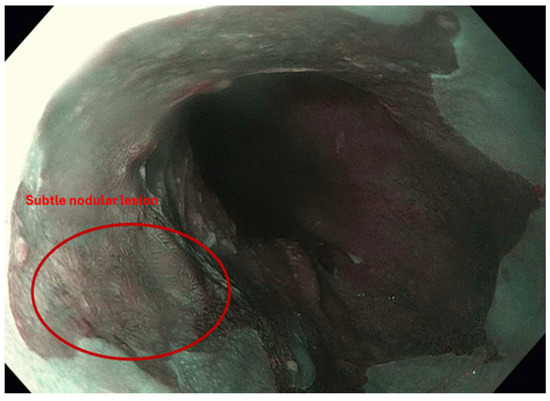

3.3.1. Role of Image Enhanced Endoscopy